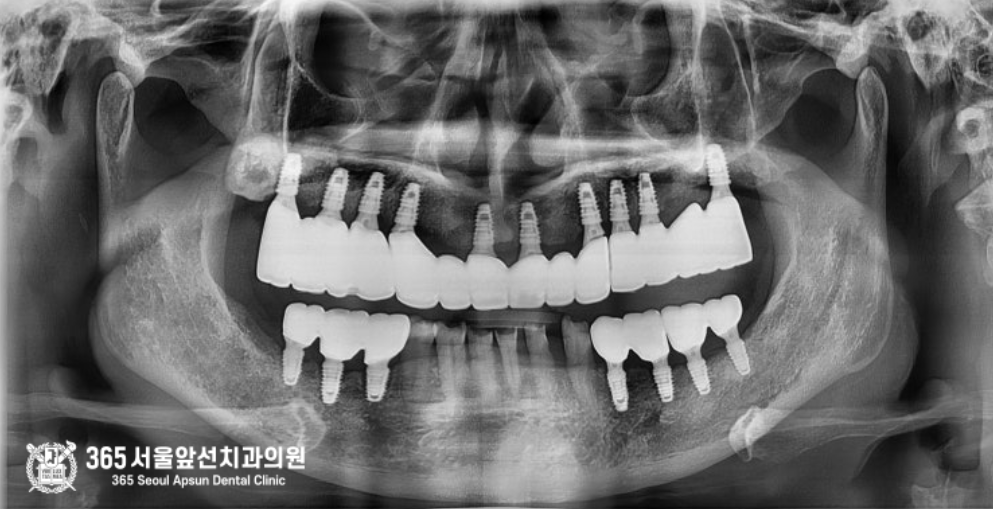

촬영일시: 2024.12.17 최종 완성 후 엑스레이 사진입니다. 환자분께서는 고통에서 벗어나 편안한 식사를 하게 되어 만족해하셨습니다 ㅎㅎ